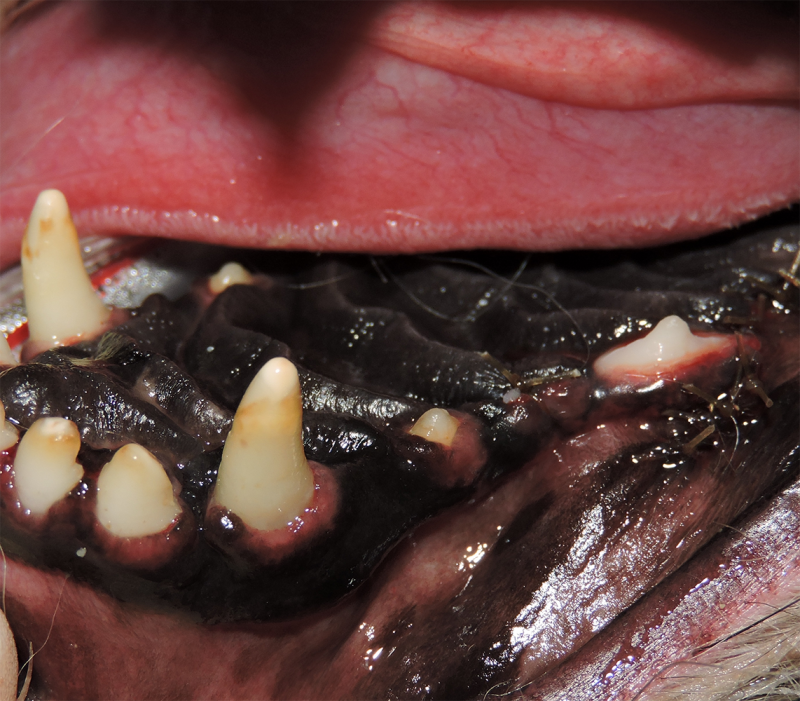

Surgical Extraction of Diseased Teeth

Periodontal disease is extremely common in dogs and cats. Over 80% of dogs and cats over two years of age have some degree of periodontal disease. Periodontal disease is best prevented by yearly professional dental cleanings starting at two years of age and at home brushing at least three times weekly. Brushing should begin at a very early age to allow your new pet to get used to regular brushing. In severe cases of infection or periodontal disease, the teeth may need to be surgically extracted. Extractions should always involve x-rays of the tooth first, as many teeth have multiple roots or may be diseased below where the eye can see. Extracting larger teeth in animals requires oral surgery, equivalent to removing wisdom teeth in people. It is vital that all of the tooth and roots be removed for the periodontal infection to resolve. In cases of important teeth with mild to moderate periodontal disease, multiple periodontal treatments can be offered to help save these teeth.

Therapy for Oral Inflammation

Dogs and cats can sometimes have severe inflammation of the mouth and gingivitis. It is not always known what the exact cause of this painful condition is, but it can be successfully managed. In cases of severe inflammation, some or all of the teeth may need to be surgically extracted. This often greatly improves the pain and inflammation in the mouth in over 80% of patients. In severe cases that do not respond to full mouth extractions, medical management can help reduce or resolve the inflammation and pain.